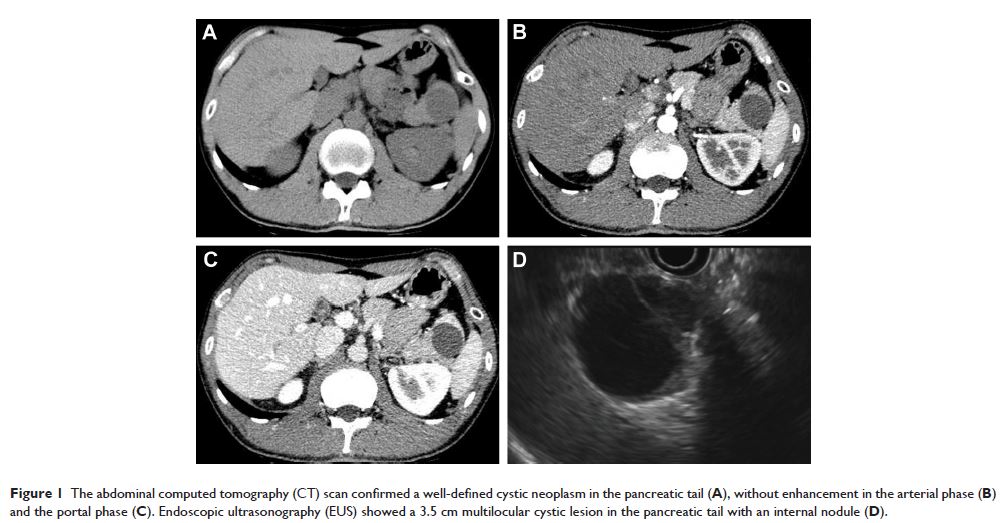

Case Report

- 作者:Bo Zhou, Qiyi Zhang, Canyang Zhan, Yuan Ding, Sheng Yan

- 期刊:Therapeutics and Clinical Risk Management